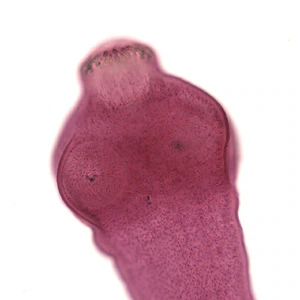

Echinococcus spp. adults.

As dogs and other canids are the definitive hosts for most Echinococcus spp. (apart from felids for E. oligarthrus), adult Echinococcus parasites are not expected to be found in the human host. Adults range from 1.2 to 7 mm in length (depending on species) and usually consist of a scolex and usually no more than six proglottids. The terminal proglottid is gravid and is longer than wide. The scolex contains four suckers and a rostellum with 25 to 50 hooks.